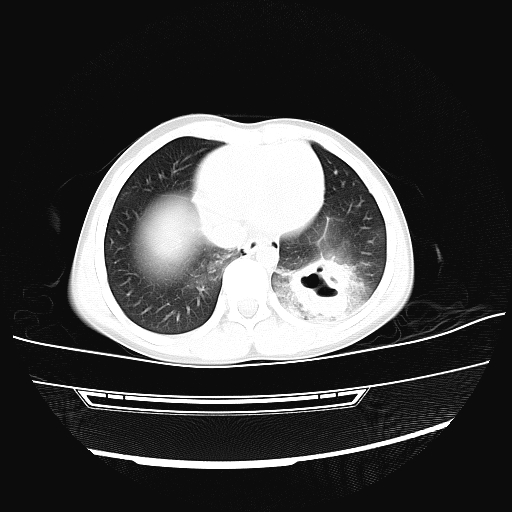

两天后复查的ct

双侧创伤性湿肺伴左下肺叶创伤性肺气囊形成

双侧创伤性湿肺,左肺挫裂伤(气血囊肿)。

肺挫裂伤并气血囊肿形成

双侧创伤性湿肺伴左下肺撕裂伤并假囊肿形成